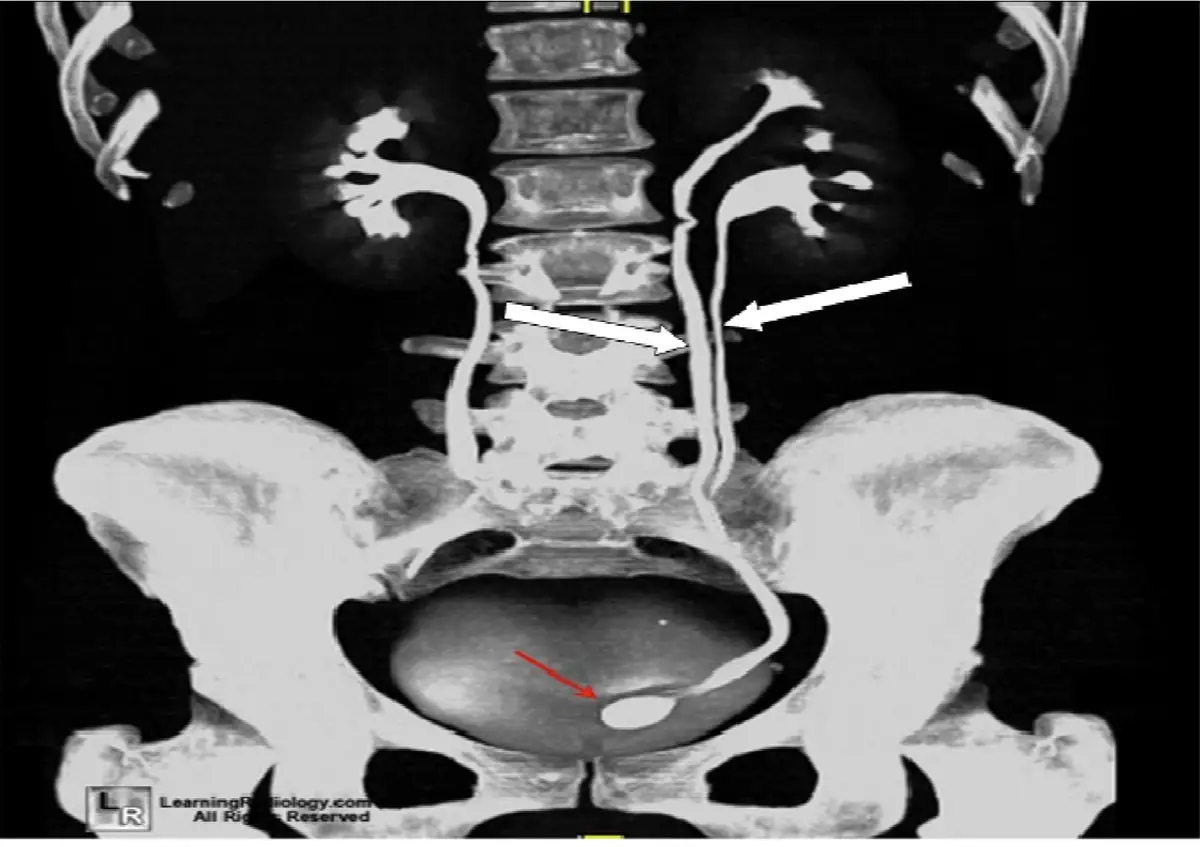

下圖為重組後腹部電腦斷層影像,白色箭號所指的為下列那一項?

影像為腹部 CT 尿路攝影的冠狀面最大強度投影(maximum intensity projection, MIP)重組影像,顯示雙側腎臟及輸尿管的完整走向。

主要所見:

- 影像左側(患者右側)腎臟顯示正常的單一集尿系統

- 白色大箭號指向影像右側(患者左側)腎臟至輸尿管區域,可見兩條獨立的輸尿管從同一腎臟向下走行——這是雙重集尿系統(duplicated collecting system)的典型影像表現

- 兩條輸尿管在腰椎旁清楚分開走行,走向骨盆腔

- 影像下方紅色小箭號指向膀胱內的充填缺損(filling defect),提示可能合併輸尿管囊腫(ureterocele)

- 整體為對比劑排泄期(excretory phase)影像,集尿系統呈高密度顯影

此影像特徵高度吻合腎盂輸尿管重複畸形(duplication of renal pelvis and ureter),即腎臟存在兩個獨立的腎盂與輸尿管系統。